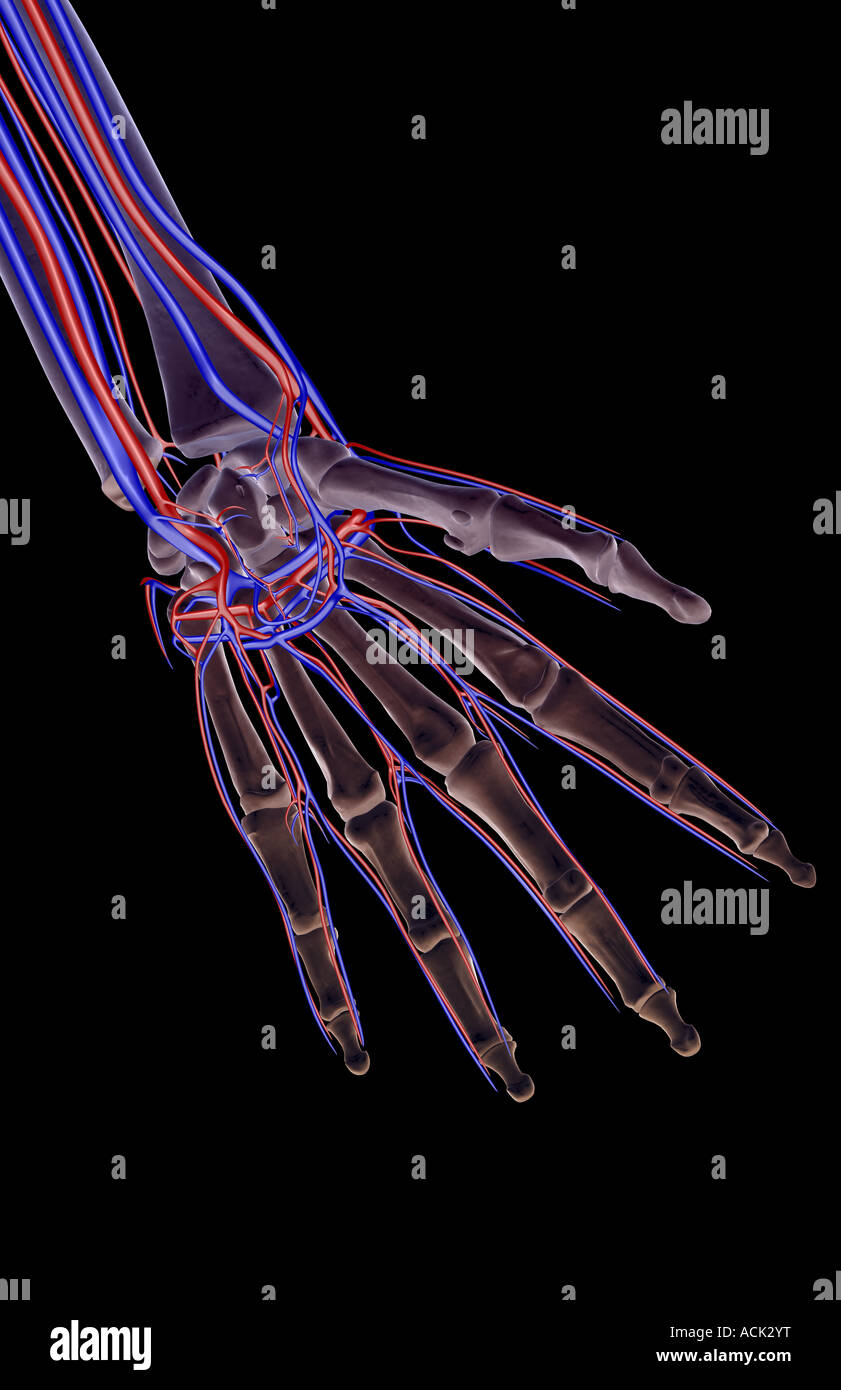

The blood supply of the hand Stock Photohttps://www.alamy.com/image-license-details/?v=1https://www.alamy.com/stock-photo-the-blood-supply-of-the-hand-13175339.html

The blood supply of the hand Stock Photohttps://www.alamy.com/image-license-details/?v=1https://www.alamy.com/stock-photo-the-blood-supply-of-the-hand-13175339.htmlRFACK2YT–The blood supply of the hand